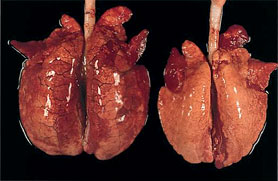

Autopsie des animaux atteints

Bien que la symptomatologie de la MAP et ses lésions macroscopiques varient, certaines découvertes d’autopsie renforcent la suspicion, voire facilitent le diagnostic de la maladie. En fait, les découvertes macroscopiques les plus représentatives de la MAP, en plus de l’amaigrissement, sont :

2. absence de collapsus pulmonaire (atélectasie), avec ou sans forme lobulaire évidente, 3. d'autres lésions macroscopiques, même moins fréquentes, peuvent être observées en cas de MAP. |

Poumons de deux animaux atteints de MAP. Celui de gauche ne présente pas d'aplatissement pulmonaire mais l'œdème interstitiel est bien visible ; ces deux lésions signent une pneumonie interstitielle. Le poumon de droite présente une consolidation pulmonaire cranio-ventrale.